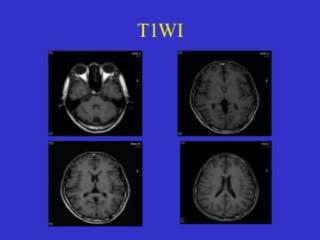

 most 'anatomical' of images- images that most closely approximate

the appearances of tissues macroscopically

 spin-lattice" relaxation time.

 demonstrates differences in the T1 relaxation times of tissues.

 relies upon the longitudinal relaxation of a tissue's net

magnetization vector (NMV).

 tends to have short TE and TR times.

 Fat quickly realigns its longitudinal magnetization with B0 - appears

bright on a T1 weighted image.

 water has much slower longitudinal magnetization realignment after

an RF pulse and therefore, has less transverse magnetization after

an RF pulse. Thus, water has low signal and appears dark.

 fat: high signal intensity (white)

 brain

› grey matter: intermediate signal intensity (grey)

› white matter: hyperintense compared to grey

matter (white-ish)

Fat – bright White matter – White

CSF – dark Gray matter - Grey